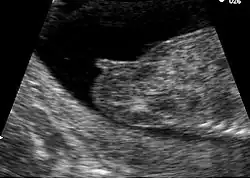

Mikroskopische Anatomie

Feingeweblich bestehen die obersten Schichten der meisten Vulvaanteile aus mehrschichtigem nichtverhornten Plattenepithel, welches in höherem Lebensalter jedoch zur Verhornung und Atrophie neigt. Die Innenseiten der inneren Schamlippen weisen ein unverhornendes, die Außenseiten ein schwach verhornendes Plattenepithel auf. Ein mehrschichtiges, meist verhorntes Plattenepithel findet sich als Bedeckung der Innenseiten, ein verhorntes an den Außenseiten der äußeren Schamlippen. In der Lamina propria des Scheidenvorhofs sind Talgdrüsen eingelagert, die einen Schutzfilm gegen die Einwirkung des Urins bilden. Solche Talgdrüsen finden sich auch in den inneren und äußeren Schamlippen. Letztere weisen zusätzlich Haarwurzelzellen, Schweißdrüsen und glatte Muskelzellen auf. Besonders viele sensible Nervenfasern und -endigungen, so etwa das Meissner-Körperchen, findet man in den Schamlippen und der Klitoris.[38][39]

-

Aufbau der weiblichen Haut (Vulva) mit ihren Hautanhangsgebilden; die Anhangsgebilde sind unterschiedlich über die jeweiligen anatomischen Strukturen verteilt -